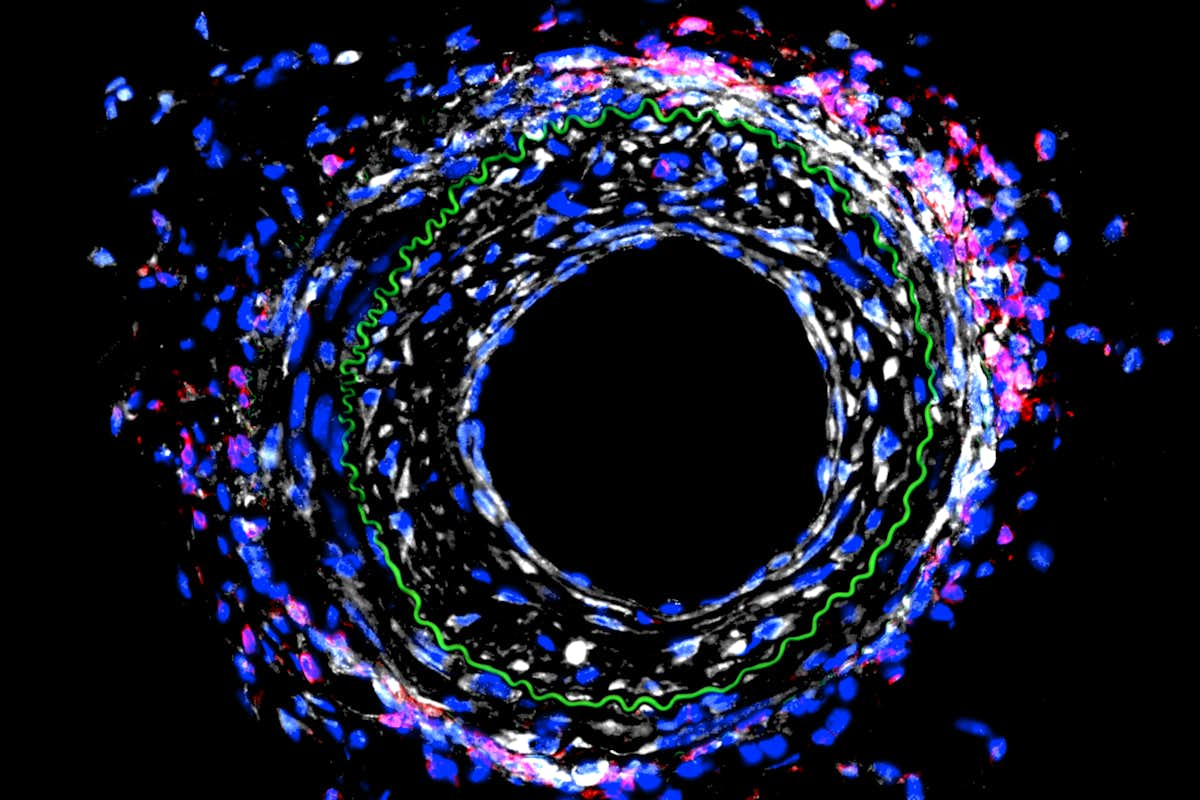

Heart attacks are caused by one or more blocked blood vessels, and physicians can restore blood flow in the heart with a stent or by bypassing the blockages with new vessels. A mechanical engineer at Washington University in St. Louis plans to take a closer look at how those blood vessels remodel in response to blocking a particular protein and the effect of that action on the immune system.

Previously, Bersi found in a mouse model that blocking activity of the cadherin-11 protein after a heart attack had a beneficial effect in the heart — the heart was not as damaged as it would have been with the protein, but had a detrimental effect on the remodeling of blood vessels.

“In the early work, we found that by modulating the activity of this protein, we’re affecting the immune system, and that change in the immune system is causing the disease to be worse in the vasculature,” Bersi said. “Now, we’re investigating the mechanisms behind that to identify new directions in the treatment of this pathology. Our hypothesis is that we would alter the immune activity contributing to the disease and reduce the vessel remodeling.”

Cadherin-11 acts as a receptor on the outside of cells that binds to and signals to other cells. This activity may lead to injuries to cells or to fibrosis, where the tissue gets stiff and hard. A heart with fibrotic tissue doesn’t function normally and can lead to heart failure.

“With a mechanical injury in a vessel wall, cells may be responding in a way that is changing how the immune system responds to that injury,” Bersi said. “We’re looking at the relationship between the mechanobiology of the tissue and immunobiology, or how the immune system responds to the mechanical responses of the cells in the tissue.”